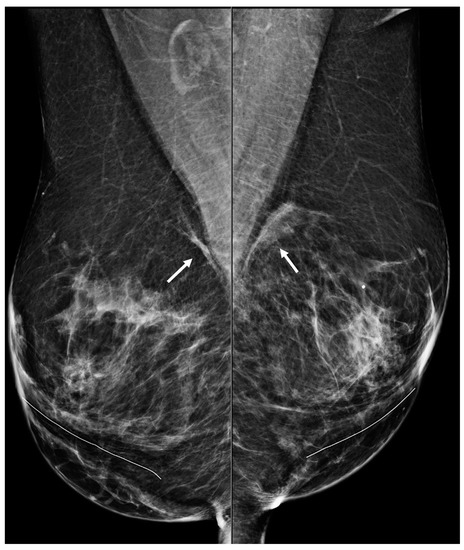

Figure 11. A 67-year-old woman with a history of subglandular silicone implants. Mammograms with bilateral CC (a) and MLO (b) views demonstrate curvilinear densities (arrows), consistent with residual implant capsules.